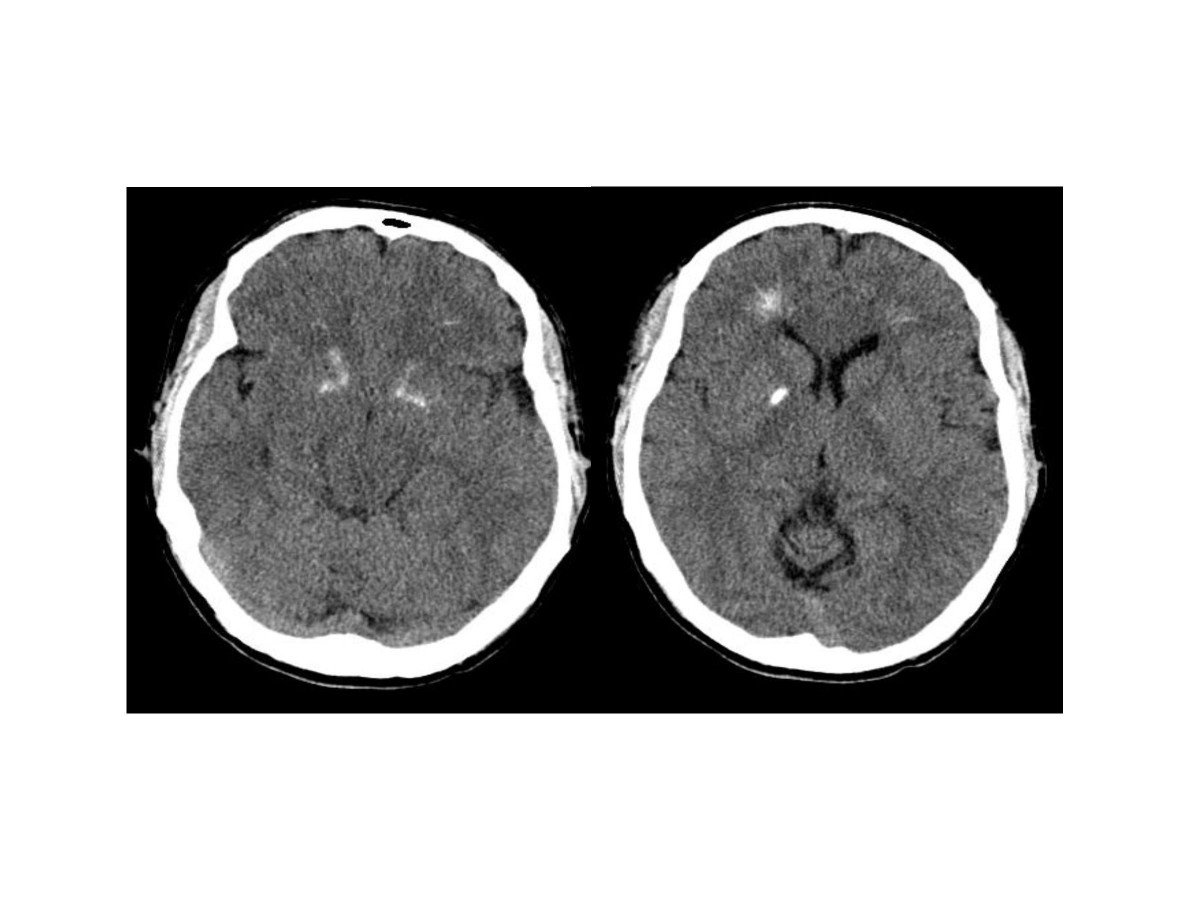

Рис. 9 Компьютерная томограмма мозга пациента с делецией